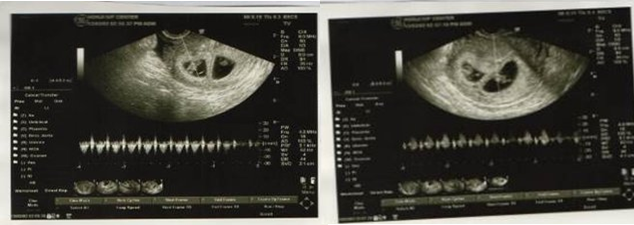

宏孕クリニックの初診では、私は2個採卵でき、それは5日保管されました。そのうち1個は胚盤胞グレードAで、1個はグレードBでした。2回目の採卵では、卵子を3個採取しました。うち2個が空砲で、別の1個は質が前回の2個に及ばないようでした。そのため、私は前回の2個を移植することに決め、無事に2個とも着床しました。今回成功したのは、刺激した卵子の数が少なかったので、卵子に多めの養分が確保でき、質が良くなったことと関係があるかもしれません。ですがそれについては、私は専門家こ方々の研究に委ねたいと思います!